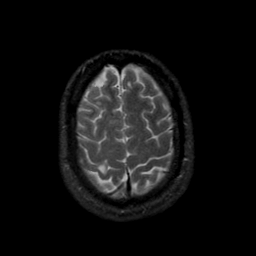

MR Study #9, April 14, 1991 -- Slice #42